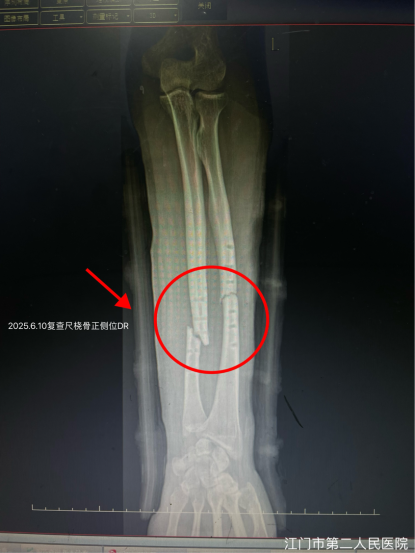

王先生1年前因左尺桡骨骨折在外院行骨折切开复位钢板螺钉内固定术。复查骨折愈合好,遂于2025.3.20返回原医院手术取出内固定。然而,术后仅1个月,在工作中搬动物品时左前臂突发剧痛,到医院检查显示左侧尺桡骨再次骨折。

经过近12周的密切诊疗和循序渐进的康复,王先生前臂肿胀疼痛迅速消退,复查X光片显示:左尺桡骨中下段呈内固定取出术后改变,断端对位对线可,骨折线由清晰逐渐模糊,肘关节、腕关节对应关系良好。

又经过2个月,再次复查,骨折断端已骨痂生长。